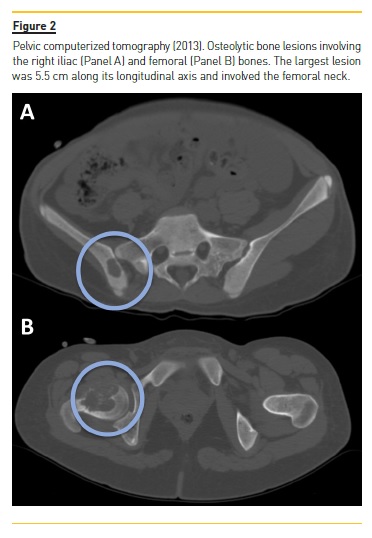

She developed CKD-MBD and maintained marginal control of PTH, calcium and phosphorus levels throughout the following years, mainly in association with low therapeutic adherence, leading to high PTH levels, frequently >1000 pg/mL. In 2013, four years after initiation of renal replacement therapy and three years after starting peritoneal dialysis, she presented right knee pain with limited range of motion which gradually worsened for two months. At that time PTH value was 1119 pg/mL. Plain radiographies revealed lytic lesions in distal femurs, proximal right femur, and right proximal tibias (Fig. 1). Computerized tomography (Fig. 2) confirmed the osteolytic bone lesions and revealed another lesion with the same features at the right iliac. The lytic lesion at right neck femur was 5.5 cm along its longitudinal axis and presented a thinned inner cortex. Computed tomography guided bone biopsy from proximal tibia was performed and documented proliferation of fibrous connective tissue and hemosiderin deposits with disperse multinucleated giant cells. These findings were compatible with brown tumors associated with severe hyperparathyroidism.